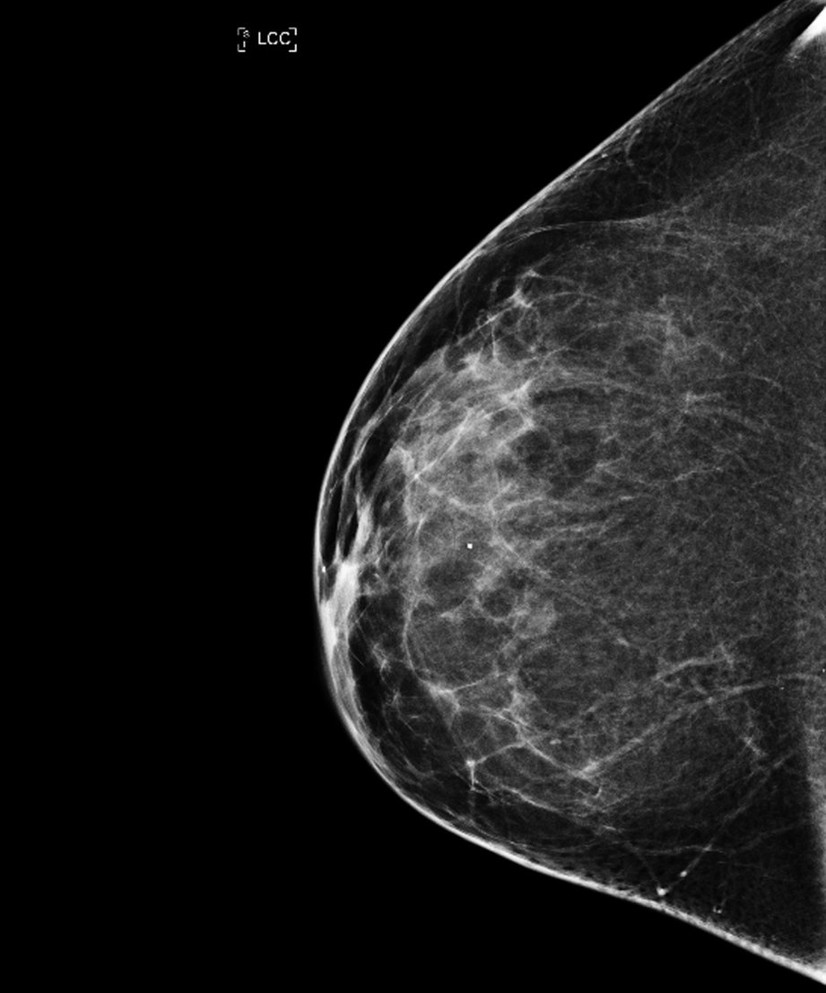

Screeningprogrammet for brystkreft har reddet Vigdis og Line Norman Hjorth. Det har også resultert i en viktig bok. Men er screening bare av det gode?